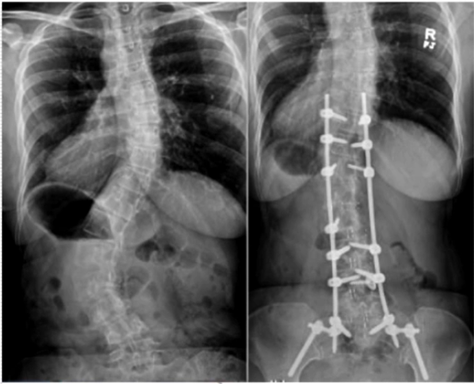

減少退變性側(cè)彎的置釘數(shù)量

對于退變性側(cè)彎/后凸畸形患者,可以選擇一期融合+二期固定的方式,可以降低置釘數(shù)量,減少對相關(guān)節(jié)段骨性結(jié)構(gòu)及軟組織的損傷。